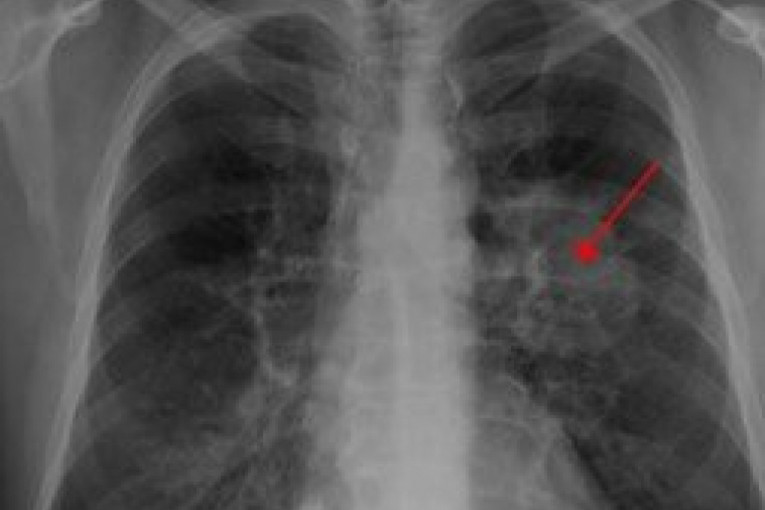

Foto: printcreen/vikipedijaTumor na plućimaKao i svaki tumor i tumor na plućima može biti benigni i maligni. Jako ga je teško prepoznati u ranoj fazi, zbog čega je u većini slučajeva neizlečiv. Osnovni faktor rizika jeste pušenje. Duvanski dim može uticati na razvoj tumora i kod pušača, ali i kod nepušača ako su mu često izloženi. Drugi faktori rizika su genetske predispozicije, udisanje štetnih gasova, kao i zagađenog vazduha. Karcinomi pluća se klasifikuju u skladu sa histološkim tipom. Ova klasifikacija je važna za utvrđivanje lečenja i predviđanje ishoda bolesti. Najveći broj slučajeva raka pluća su karcinomi — maligniteti koji nastaju iz epitalnih ćelija. Karcinomi pluća se kategorišu prema veličini i obliku malignih ćelija koje histopatolog vidi pod mikroskopom. Simptomi raka pluća su kašljanje (uključujući iskašljavanje krvi), gubitak telesne težine, kratkoća daha, groznica, krivljenje noktiju, ili umor, kostobolja, opstrukcija gornje šuplje vene, otežano gutanje. U svetu, rak pluća je najčešći tip raka u pogledu incidence i mortaliteta. U 2008. godini, bilo je 1,61 miliona novih slučajeva i 1,38 miliona smrtnih slučajeva uzrokovano rakom pluća. Najveće su stope u Evropi i Severnoj Americi, a kako prenose statistike, svega 15% obolelih preživi pet godina od postavljanja dijagnoze. |